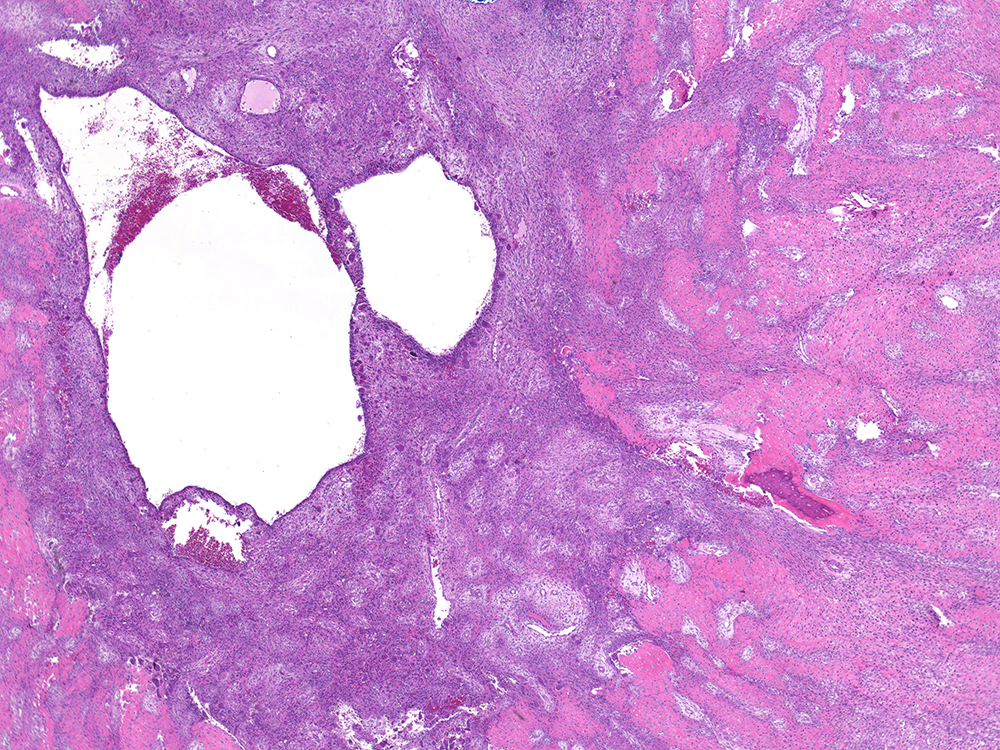

1) alveolar rhabdomyosarcoma

2)

Fibrovascular cores

Nests of small blue round tumor cells looking dyscohesive at the edge because they are fragmented

Strap cells (elongated eosinophilic like immature muscle cells) sometimes seen

Multinucleated wreath cells (peripheral multimuclei, muscle differentiarion)

Rhabdomyoblasta

3)

SBRCT

Embryonal rms (less aggressive)

4) children and young adults

5)

Desmin+

MyoD + Myogenin+

6) t(1;13) or t(2;13) = PAX3-FOXO1 or PAX7-FOXO1